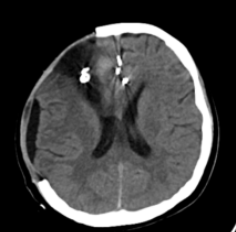

▲术后复查头部CT显示颅内血肿清除且无再次出血现象。